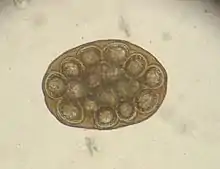

Adult morphology

The adult worm is about 18 inches (46 cm) long. Gravid proglottids containing the worm's microscopic eggs are either passed in the definitive host's feces or may leave their host spontaneously and are then ingested by microscopic flea larvae (the intermediate hosts) in the surrounding environment. As in all members of family Dipylidiidae, proglottids of the adult worm have genital pores on both sides (hence the name double-pore tapeworm). Each side has a set of male and female reproductive organs. The uterus is paired with 16 to 20 radial branches each. The scolex has a retractable rostellum with four rows of hooks, along with the four suckers that all cyclophyllid cestodes have.